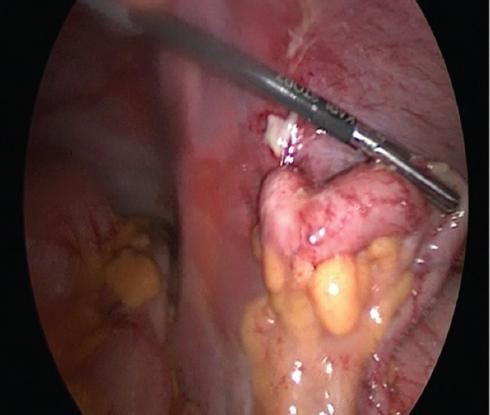

Cirugía realizada: apendicectomía laparoscópica. Abordaje con técnica de Hasson a través de una incisión umbilical de 1 cm, posteriormente se coloca un trocar umbilical de 12 mm y se inicia capnoperitoneo hasta 12 mmHg. Se introduce una lente de 30° y se realiza laparoscopia diagnostica. Se procede a la colocación de trocares de 5 mm, de región suprapúbica y de flanco izquierdo.

Hallazgos: adherencias laxas del epiplón a la pared. Líquido libre purulento de aproximadamente 20 ml. Apéndice vermiforme de 10 cm, hiperémico, edematoso en toda su extensión, con placas fibrinopurulentas. Se realiza apendicectomía y se maneja el muñón con técnica de Halsted. Sin complicaciones, con sangrado mínimo (Figs. 2 and 3).